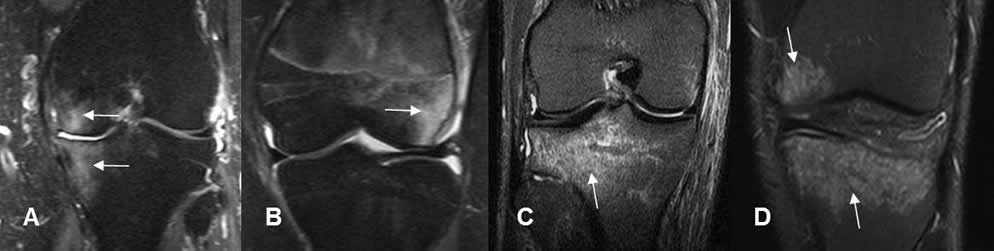

Fig 28. Mecanismo del trauma directo.

A: RM coronal en STIR. Contusión osea en el compartimiento medial, que puede lesionar las estructuras de la esquina posterolateral y el LCL.

B: RM coronal en STIR. Contusión del cóndilo femoral lateral, debiendo descartar lesión del LCM.

C: RM coronal en STIR. Contusión en la parte posterior de la tibia, por lo que se debe buscar lesión del LCA

D: Contusión en la parte anterior de la tibia y cóndilo femoral medial, a descartar lesión del LCP y esquina posterolateral.